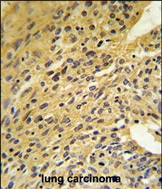

- COQ5 Antibody (Center) (Cat. #P30490) IHC analysis in formalin fixed and paraffin embedded human lung carcinoma followed by peroxidase conjugation of the secondary antibody and DAB staining. This data demonstrates the use of the COQ5 Antibody (Center) for immunohistochemistry. Clinical relevance has not been evaluated.